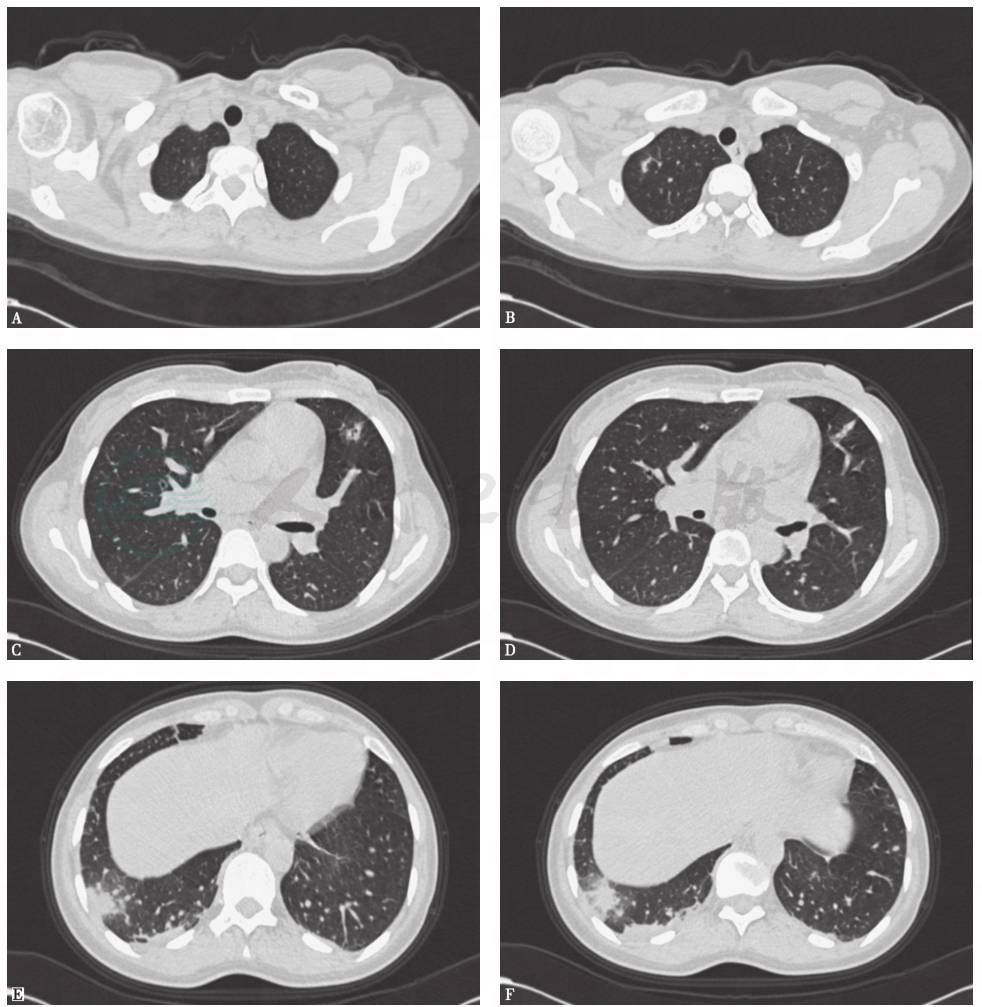

胸部CT(2014年12月23日):双肺散在结节影,边界模糊,右肺上叶见薄壁空洞影,未见肺门和纵隔淋巴结肿大,未见双侧胸膜积液(图2)。

图2 胸部CT表现(2014-12-23)

胸部CT(2015年1月23日):双肺内散在斑片状高密度影较前有所吸收,右肺下叶斑片影可见小空洞形成,双侧胸腔积液吸收、好转(图4)。

图4 胸部CT表现(2015-01-23)